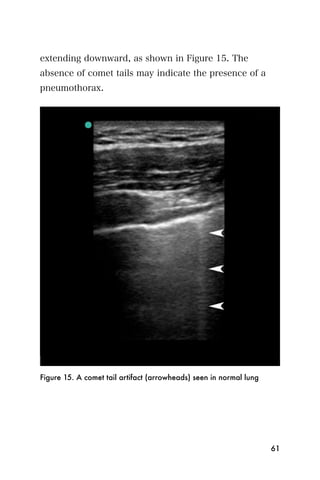

Comet Tail Artifacts

Artifacts that normally arise from interlobar septae

under the visceral pleura. Comet tails appear as

hyperechoic lines beginning at the pleural line and

60

extending downward, as shown in Figure 15. The

absence of comet tails may indicate the presence of a

pneumothorax.

Figure 15. A comet tail artifact (arrowheads) seen in normal lung